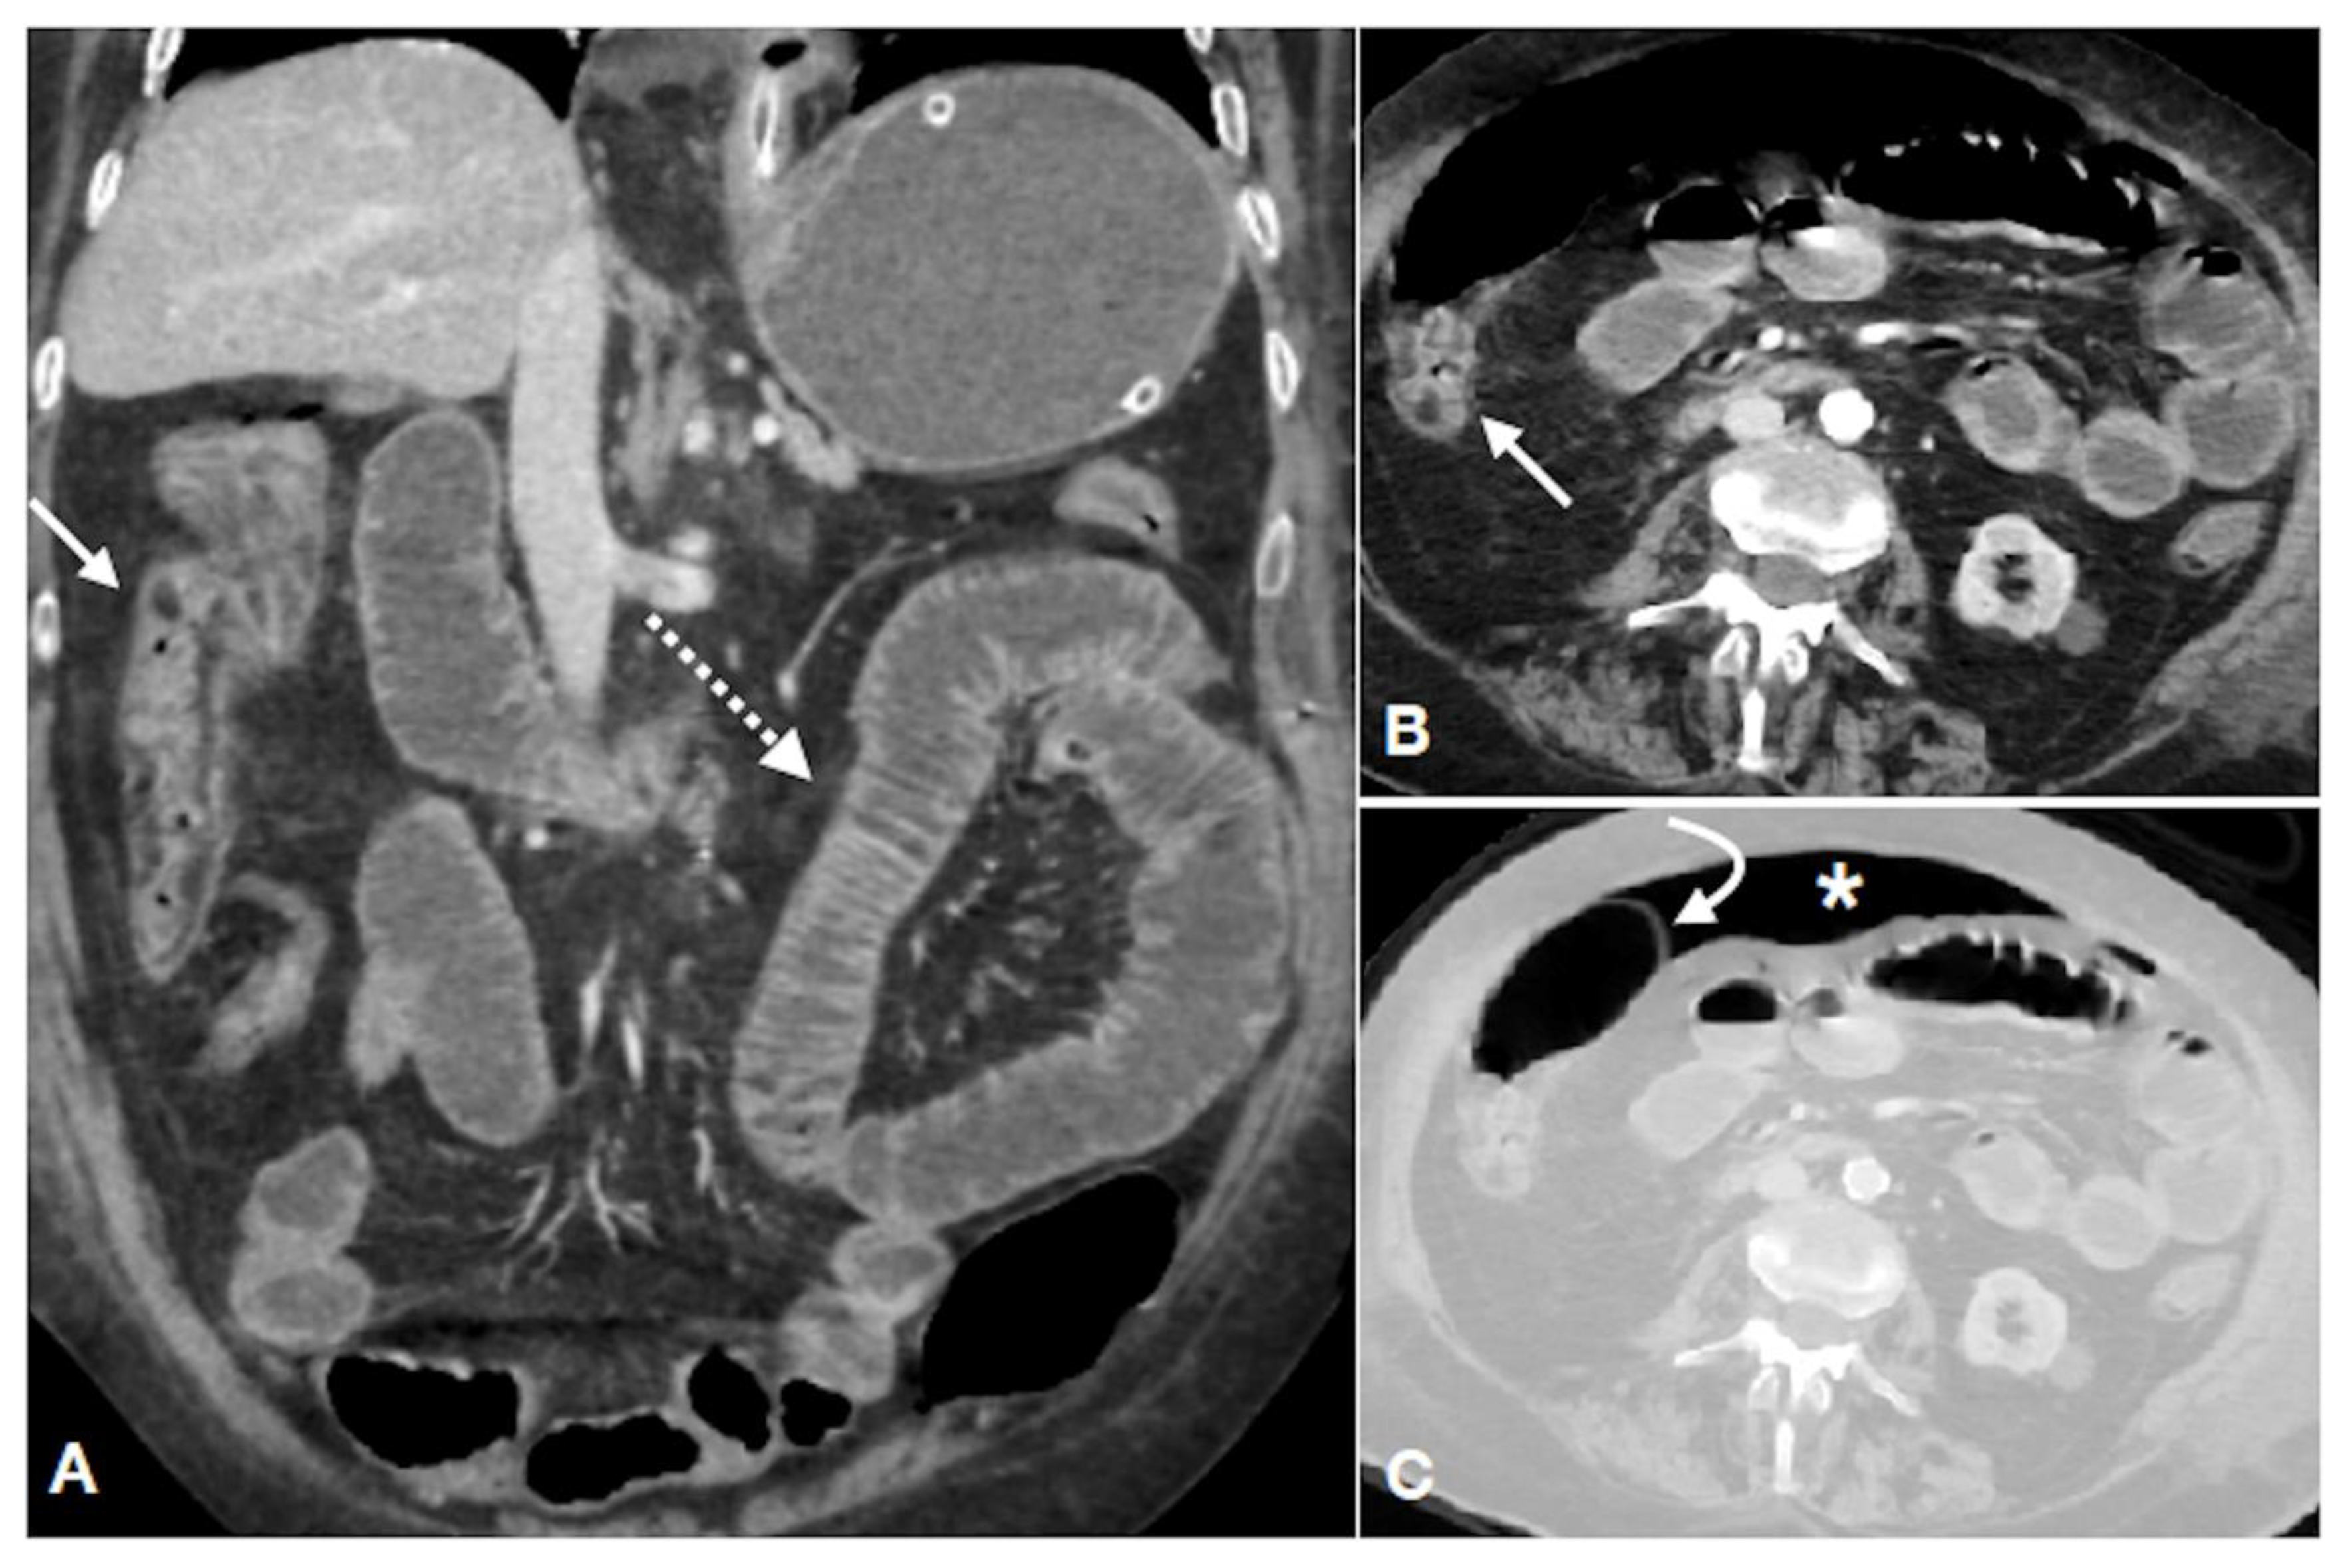

| Damage | Radiological Findings and Characteristics |

|---|---|

| Type of damage Arterial ischemic type (less frequent) Reperfusive type (more frequent) Venous congestion (rare) | Thin or “paper thin” colonic wall; |

| Unenhanced colonic wall at enhanced CT; | |

| Dilation of the lumen, only gas-filled; | |

| Wall pneumatosis; | |

| Pneumoperitoneum; | |

| Parenchymal ischemia of liver/kidney/spleen; | |

| SMA/IMA or relative branches obstruction; | |

| Peritoneal/retroperitoneal free fluid (late finding); | |

| Thickened colonic wall; | |

| Mucosal hyperdensity (“little rose” sign); | |

| Lumen caliber reduction; | |

| Stratified enhanced wall (“target sign”); | |

| Fat stranding; | |

| Pericolic fluid; | |

| SMV/IMV or relative branches obstruction; | |

| Bowel wall findings similar to the reperfusive type; | |

| Peritoneal/retroperitoneal free fluid | |

| Location of the damage | Descending colon; |

| Sigmoid colon; | |

| Right colon; | |

| Entire colon | |

| Extension of the damage | Single segment involvement; |

| Multisegmental pattern: | |

| Contiguous multisegmental involvement | |

| Skipped segments involvement | |